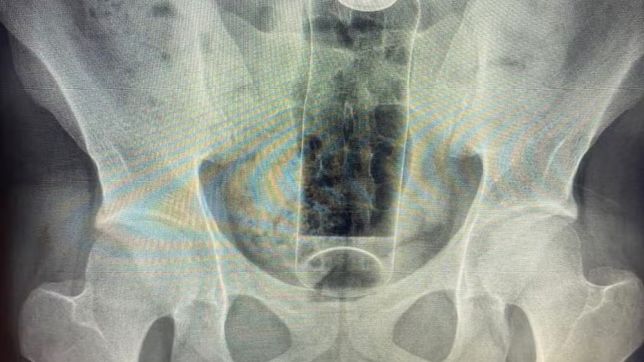

Um jovem de 19 anos precisou ser internado após um desodorante ficar preso em seu reto durante uma prática sexual. O caso foi divulgado por um médico nas redes sociais como forma de alerta sobre os riscos do uso de objetos inadequados na exploração da sexualidade, especialmente da região anal.

De acordo com o cirurgião coloproctologista Daniel Brosco, responsável pelo atendimento, o paciente relatou que introduziu o desodorante no ânus durante uma “brincadeira” íntima. No entanto, o objeto acabou sendo sugado para dentro do reto e não pôde ser removido em casa, exigindo intervenção hospitalar.

Paciente ficou com desodorante preso no reto